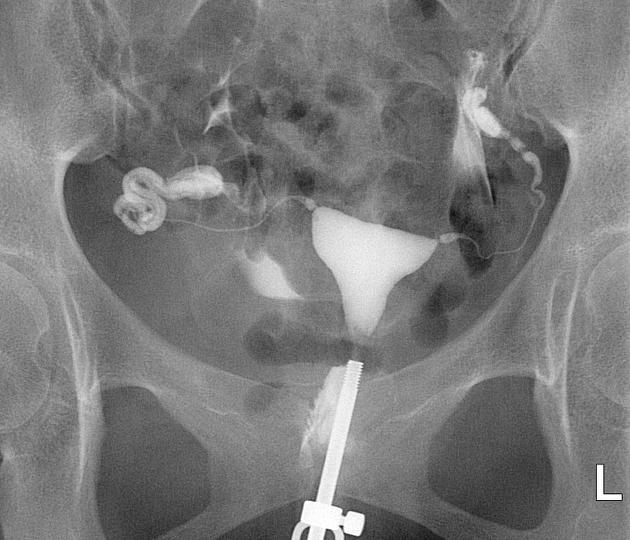

Гистеросальпингография: описание и фотографии